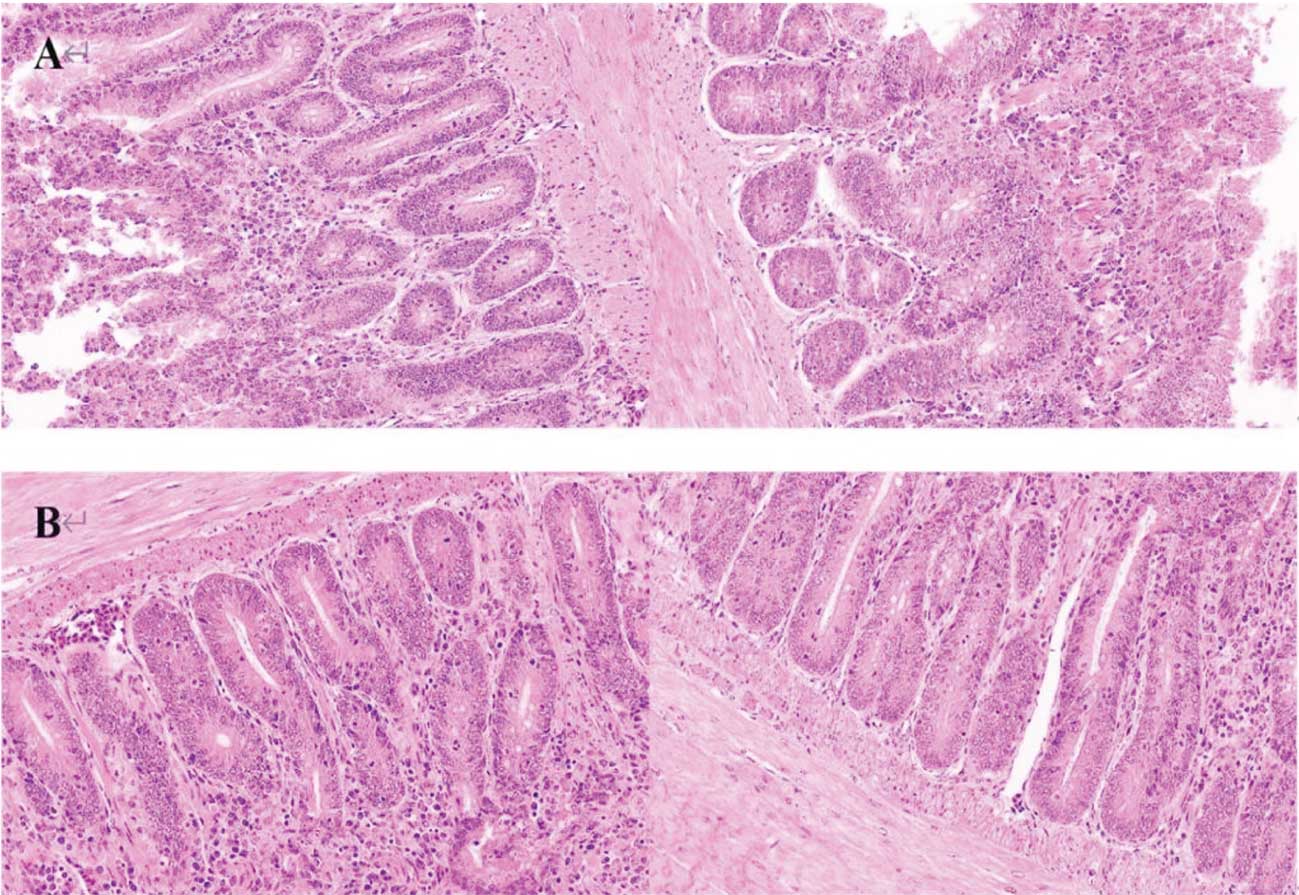

Gambar 3. Histologi duodenum yang menunjukkan jumlah sel inflamasi yang secara signifikan lebih tinggi pada kelompok kontrol (A) dibandingkan dengan kelompok yang diberi perlakuan tryptophan (B).

Sumber: Ma et al. (2024).

Secara keseluruhan, penelitian tersebut menyimpulkan bahwa suplementasi tryptophan dalam pakan dapat membantu melindungi kesehatan usus pada ayam broiler yang terpapar fotoperiode panjang dengan cara menekan aktivasi inflammasome NLRP3. Efek ini tampaknya dimediasi melalui perubahan metabolit turunan tryptophan serta komposisi mikrobiota usus. Dengan demikian, suplementasi tryptophan dapat menjadi strategi nutrisi yang menjanjikan untuk menjaga kesehatan usus dalam sistem produksi intensif yang menggunakan program pencahayaan yang diperpanjang (Ma et al., 2024).